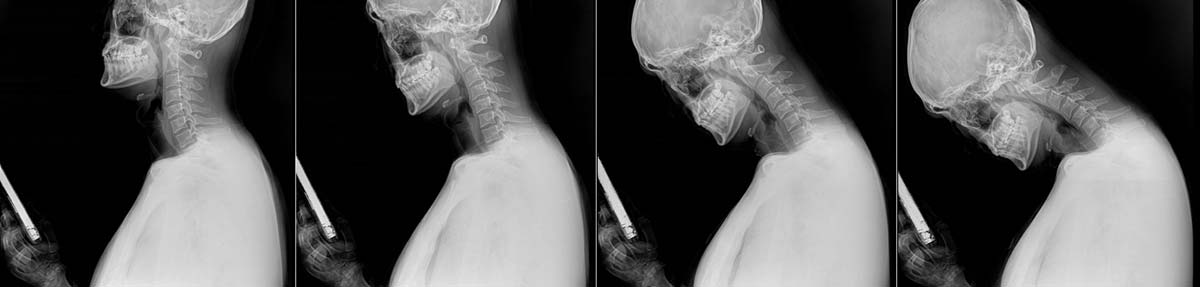

- 거북목 증후군 및 목디스크: 고개를 숙이고 스마트폰을 내려다보는 자세는 목에 가해지는 무게를 머리 무게의 5배 이상으로 증가시킵니다. 이는 경추의 C자 커브를 일자나 역 C자로 변형시켜 두통, 어깨 통증, 심하면 팔 저림을 동반한 목디스크를 유발합니다. (💡 참고: 고개 숙일 때 목에 가해지는 부담)